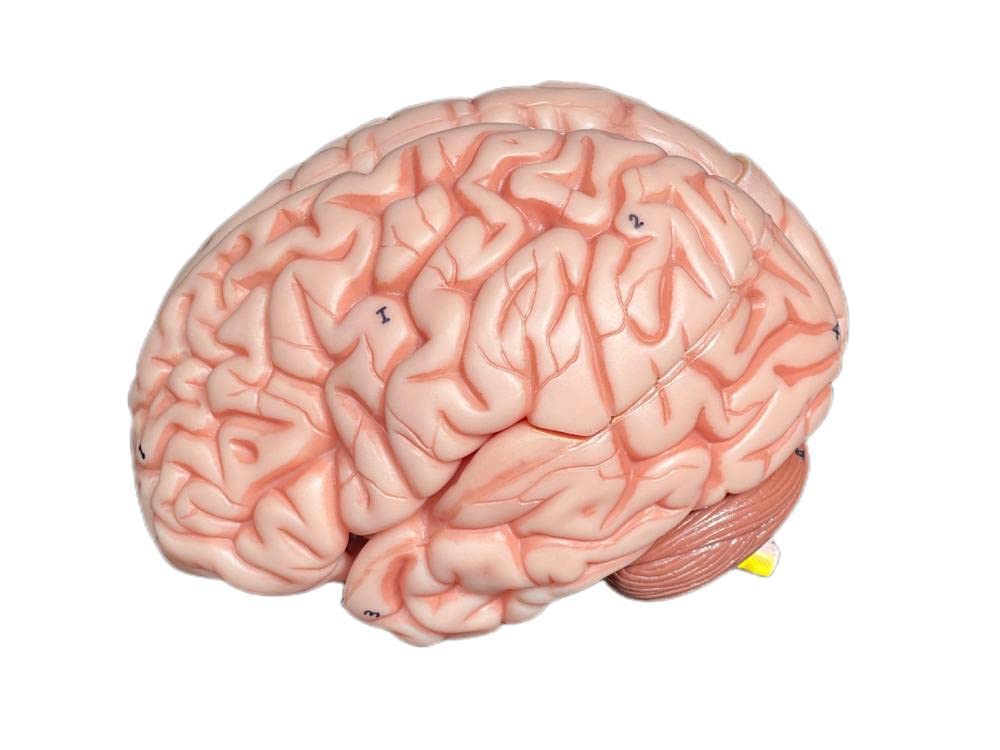

This model is cast from a high-quality original specimen. The classic skull is medically detailed in structure. It has highly accurate representation of the fissures, foramina, processes, sutures etc. Skull is 3-part: Skull Cap, Base of Skull and Mandible. The mandible is articulated on springs to demonstrate natural movements. Use this unique transparent replica of the human skull to study internal structures that otherwise are visible only through x-ray images. Brain separates into 8 parts: frontal and parietal lobes (2), temporal and occipital lobes (2), medulla (2), cerebellum (2). Structures are shown in great detail with about 30 features marked with numbers. Number key is provided. A great addition to any educational collection. Size: Life size Measurement: 22X13X17cm Weight: 2 kgs Material: high quality PVC

- The brain can be disassembled into 8 parts.